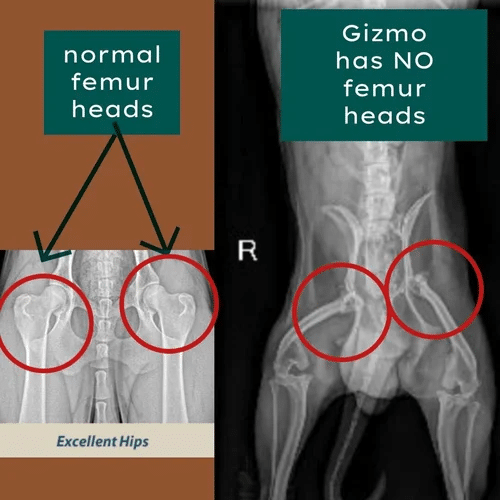

Gizmo

Gizmo’s Story